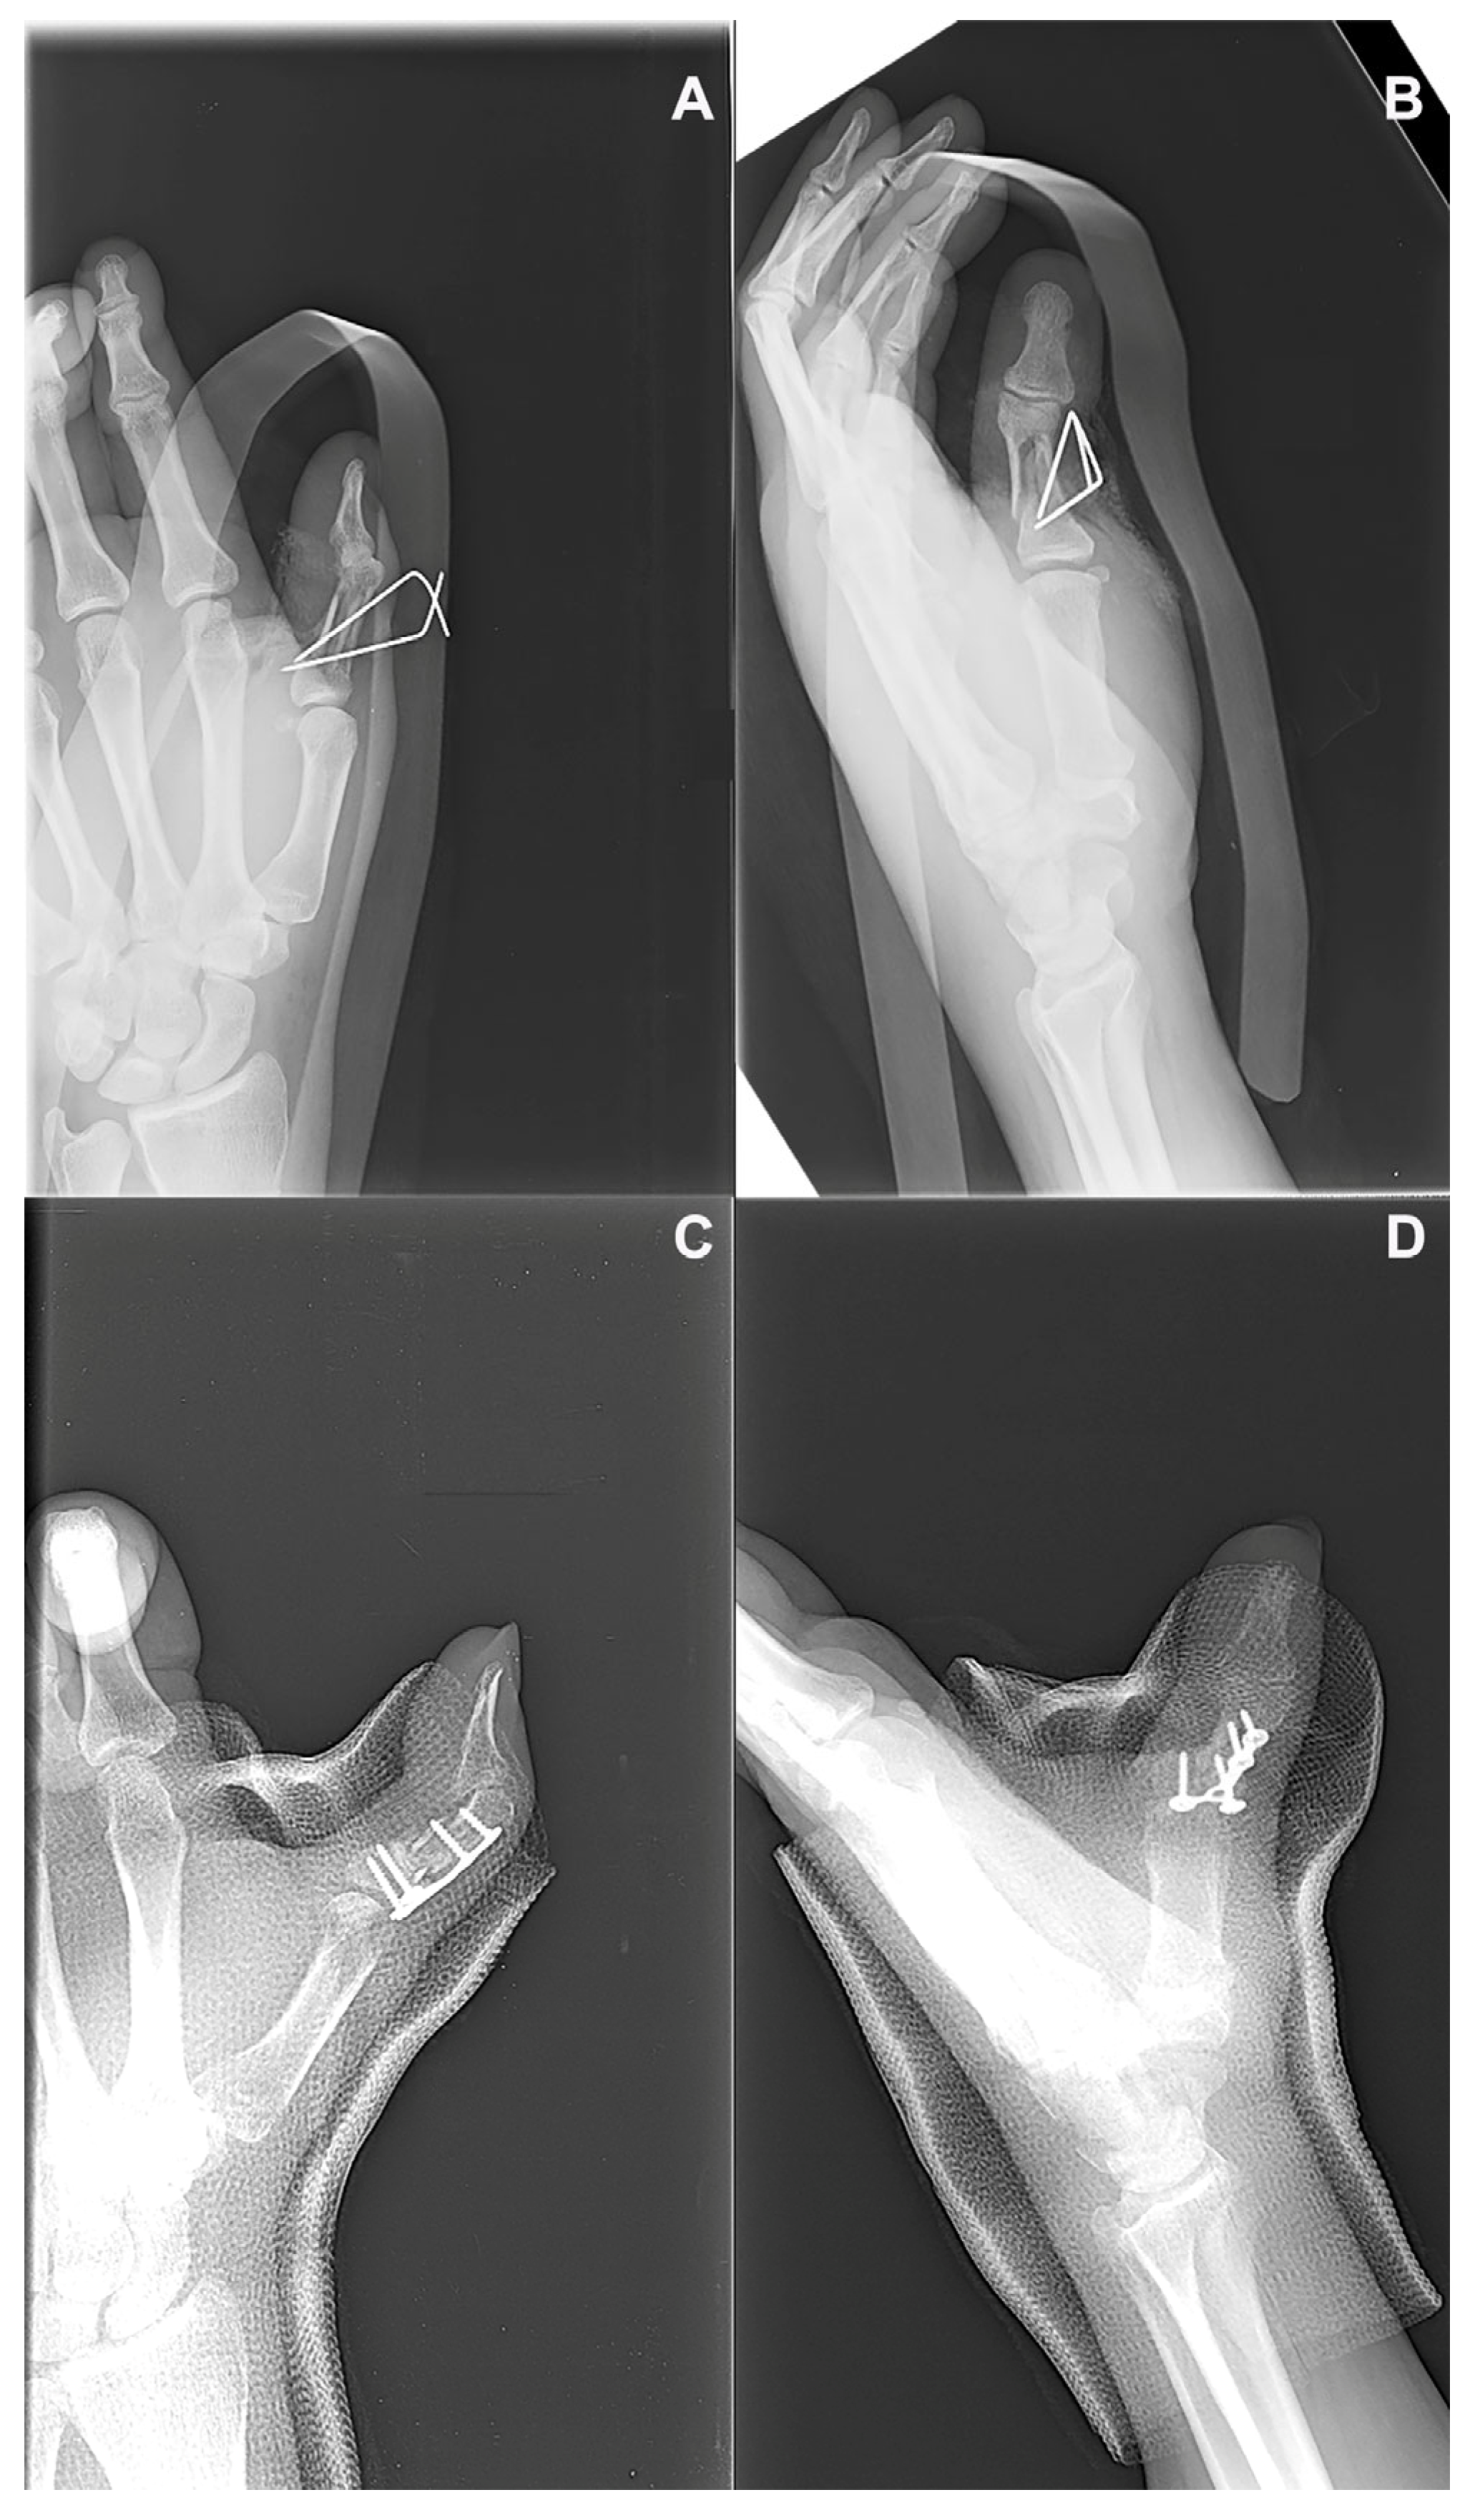

A 51-year-old right-handed male presented with persistent pain and limited functional capacity of the dominant hand, six months after a direct hand trauma that resulted in a diaphyseal fracture of the thumb phalanx (P8). The initial treatment had consisted of surgical fixation with Kirschner wires, but radiographs at follow-up showed an absence of bridging callus and sclerotic margins at the fracture site, consistent with an atrophic nonunion (Figure 6A,B). A regenerative strategy was undertaken as a first-line reconstructive approach, aimed at enhancing the biological environment. Surgical re-entry was performed through the original incision. The nonunion site was debrided meticulously to remove fibrous tissue and expose bleeding bone margins. A tricortical bone graft was harvested from the iliac crest and processed with the Rigenera® system to obtain autologous cancellous micro-grafts. These micro-grafts, rich in viable osteoprogenitor cells and growth factors, were implanted into the nonunion site and integrated with the structural graft. Fixation was reinforced using a new low-profile plate to ensure stability during the osteointegration phase. A fresh amniotic membrane was rehydrated and wrapped around the grafted area, secured with microsurgical sutures to form a biological regenerative chamber. Postoperative management included early protected mobilization and edema control. After one postoperative month, radiographs confirmed complete consolidation (Figure 6C,D). At 3-month follow-up, the patient exhibited a Total Active Motion (TAM) of 110 degrees for the thumb, corresponding to an 84.6% recovery based on a theoretical maximum of 130°, thus indicating a “good” outcome according to the adapted American Society for Surgery of the Hand (ASSH) criteria for thumb function. A residual coronal plane deviation of 10 degrees and a fixed flexion contracture of 15 degrees at the proximal interphalangeal (PIP) joint were observed. Despite these findings, grip strength was 46 kg, pinch strength was 6 kg, and pain was nearly absent (VAS 1). No complications were recorded. Functional evaluation using the Buck-Gramcko method, adapted for the thumb, yielded an estimated score of 15/15, classifying the outcome as “excellent”. However, it is important to note that this score may underestimate certain functional limitations, such as minor joint deviation or specific activity-related deficits, which are not captured by this scoring system despite their clinical relevance. The outcome was rated as “good” by both patient and surgeon, with satisfactory functional recovery.

Figure 6. Radiographic images of the third metacarpal fracture site: (A,B) Preoperative anteroposterior and oblique views showing an atrophic nonunion characterized by the absence of bridging callus and sclerotic fracture margins, four months after initial fixation. (C,D) Postoperative radiographs obtained one month after the regenerative procedure, demonstrating progressive graft integration and early signs of fracture healing.